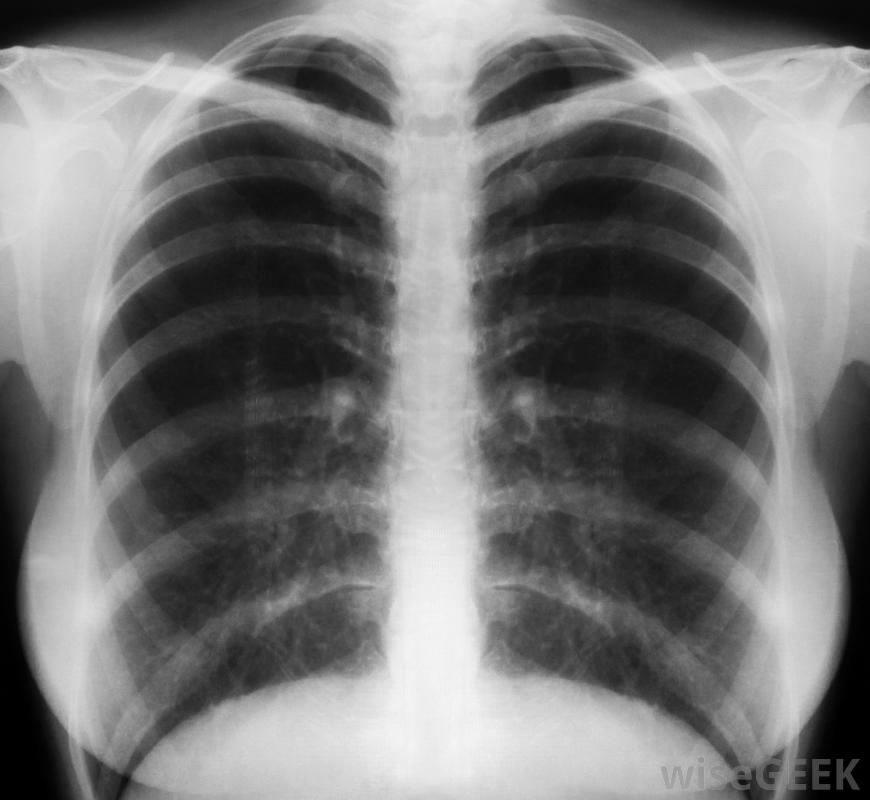

慢性哮喘是一種持續的氣道炎癥和刺激性疾病。當外界因素如冷空氣或過敏原存在時,哮喘患者會出現氣喘、咳嗽和呼吸急促的急性發作。哮喘發作可持續幾分鐘到24小時以上,輕微的呼吸困難可能會在兩次發作之間持續存在。慢性哮喘通常是一種遺傳性疾病,在兒童晚期或青春期趨于好轉,盡管許多人有終生的癥狀。醫生可以在急性發作期間開藥擴張氣道,以幫助預防將來的發作患有慢性哮喘的人應該保持吸入器,慢性哮喘患者的肺部和氣道始終處于吸入器狀態受到一定程度的刺激。由于肺活量有限和粘液堆積,一些患者無法深呼吸。在發作期間,炎癥惡化,氣道嚴重收縮。身體對炎癥的自然反應是增加粘液的生成,從而進一步阻塞氣道。患者體驗到胸痛氣喘,咳嗽和呼吸急促。疼痛和呼吸系統問題可導致脈搏加快和失去意識,在最嚴重的情況下。暴露在空氣污染中可能增加一個人患哮喘的幾率有慢性哮喘家族史和過敏史的人很可能會遺傳這種疾病。兒童時期嚴重的呼吸道感染、多年的空氣污染和肥胖也是發展哮喘的重要危險因素,空氣中的過敏原或其他環境因素會導致急性發作。寵物皮屑、霉菌、煙霧和花粉等過敏原進入呼吸道,引發炎癥、咽喉阻塞和粘液生成。有些人在寒冷天氣鍛煉或外出時哮喘加重哮喘患者也會成為某些過敏癥的受害者,醫生可以通過進行一系列的診斷試驗。醫生用聽診器聽病人的胸部,并指導他向一種稱為峰值流速計的裝置吹氣以測量肺活量。經常進行胸部x光檢查,以便醫生更好地評估炎癥和氣道阻塞的嚴重性患有慢性哮喘的兒童可以接受呼吸治療。有許多短期和長期治療選擇適用于哮喘發作頻繁的人群病人通常會得到處方或非處方吸入器,稱為支氣管擴張劑。吸入器含有大量的皮質類固醇,在急性發作時可以放松喉嚨的肌肉,減少炎癥。經常發作的病人可以開口服消炎藥或專門的藥物每天使用吸入器。此外,醫生可以提供有關避免某些環境因素和限制劇烈運動的信息,以幫助預防慢性哮喘癥狀。咳嗽可能是哮喘發作的一部分哮喘吸入器。兒童肥胖是發展慢性哮喘的危險因素經常使用胸部x光片,這樣醫生可以更好地評估哮喘的嚴重性慢性過敏可導致哮喘醫生可以通過傾聽患者的聲音來判斷哮喘的嚴重程度;有慢性哮喘家族史的人很可能遺傳這種疾病。